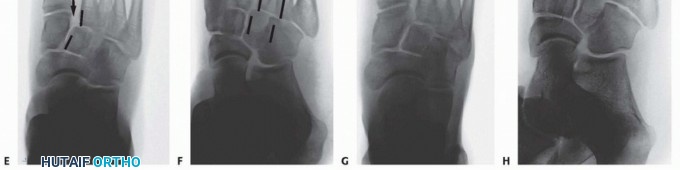

Initial radiographic evaluation consists of non-weight-bearing anteroposterior (AP), oblique, and lateral views of the foot, which, depending on the extent of intra-articular displacement, may provide sufficient diagnostic information (

FIG 3A-C

).

Fluoroscopic stress views may be helpful in more subtle injuries; however, these studies are painful and generally require anesthesia.

We therefore prefer weight-bearing radiographs of the foot for more subtle injuries (

FIG 3D-H

); comparison weight-bearing radiographs of the contralateral foot may also be obtained where necessary.

The weight-bearing AP view of the foot will demonstrate intra-articular displacement through the first and second tarsometatarsal joints (so-called Lisfranc joint), intercuneiform joint, and naviculocuneiform joint; fractures through the first and second metatarsal bases, medial and middle cuneiforms, and proximal extension into the navicular; and the extent of columnar shortening or asymmetry.

The medial border of the second metatarsal should align with the medial border of the middle cuneiform (

FIG 3D

The oblique view will reveal intra-articular displacement through the third, fourth, and fifth tarsometatarsal joints and fractures of the third, fourth, and fifth metatarsal bases, lateral cuneiform, and cuboid.

The medial borders of the third and fourth metatarsals should align with the medial borders of the lateral cuneiform and cuboid, respectively (

FIG 3E

The lateral view may reveal dorsal-plantar displacement of fractures or dislocations as well as any flattening of the medial longitudinal arch, thereby reflecting the status of the weight-bearing medial column and first ray (

FIG 3F

FIG 3

• Non-weight-bearing AP (

A

), oblique (

B

), and lateral (

C

) radiographs of grossly unstable, purely ligamentous, Lisfranc dislocation involving all five tarsometatarsal articulations. Marked lateral subluxation through all five tarsometatarsal joints is evident on the AP and oblique views, and significant dorsal displacement is evident on the lateral view. Weight-bearing lateral (

D

), AP (

E

), and oblique (

F

), and non-weight-bearing (

G

) and oblique (

H

) radiographs of more subtle Lisfranc injury. Lateral and plantar subluxation (

black arrows

) is evident on the weight-bearing radiographs, and displacement of normal radiographic landmarks (

black lines

) confirms injury.